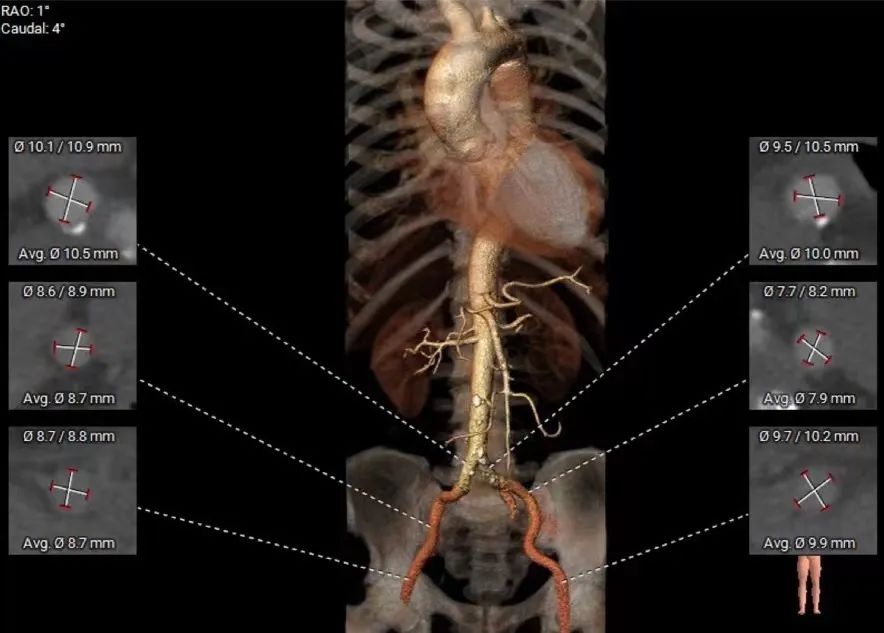

术前CT评估

• Type1型二叶式主动脉瓣,瓣环径为28.1mm,瓣环明显增大,瓣叶增厚伴重度钙化,钙化延续左室流出道,左冠窦单叶瓣畸形,LVOT敞口;

• 冠脉开口高度可,切线角度测量未见冗长瓣叶;

• 瓦氏窦、窦管交界内径尚可,升主动脉扩张;

• 左室腔内径明显增大,心室壁厚度尚可;

• 瓣环水平夹角为58°,主动脉弓宽度、角度尚可;

• 主动脉弓、腹主动脉下段、双侧髂总动脉可见散在钙化斑块,双侧股髂动脉未见明显扭曲,股动脉穿刺处未见钙化斑块。